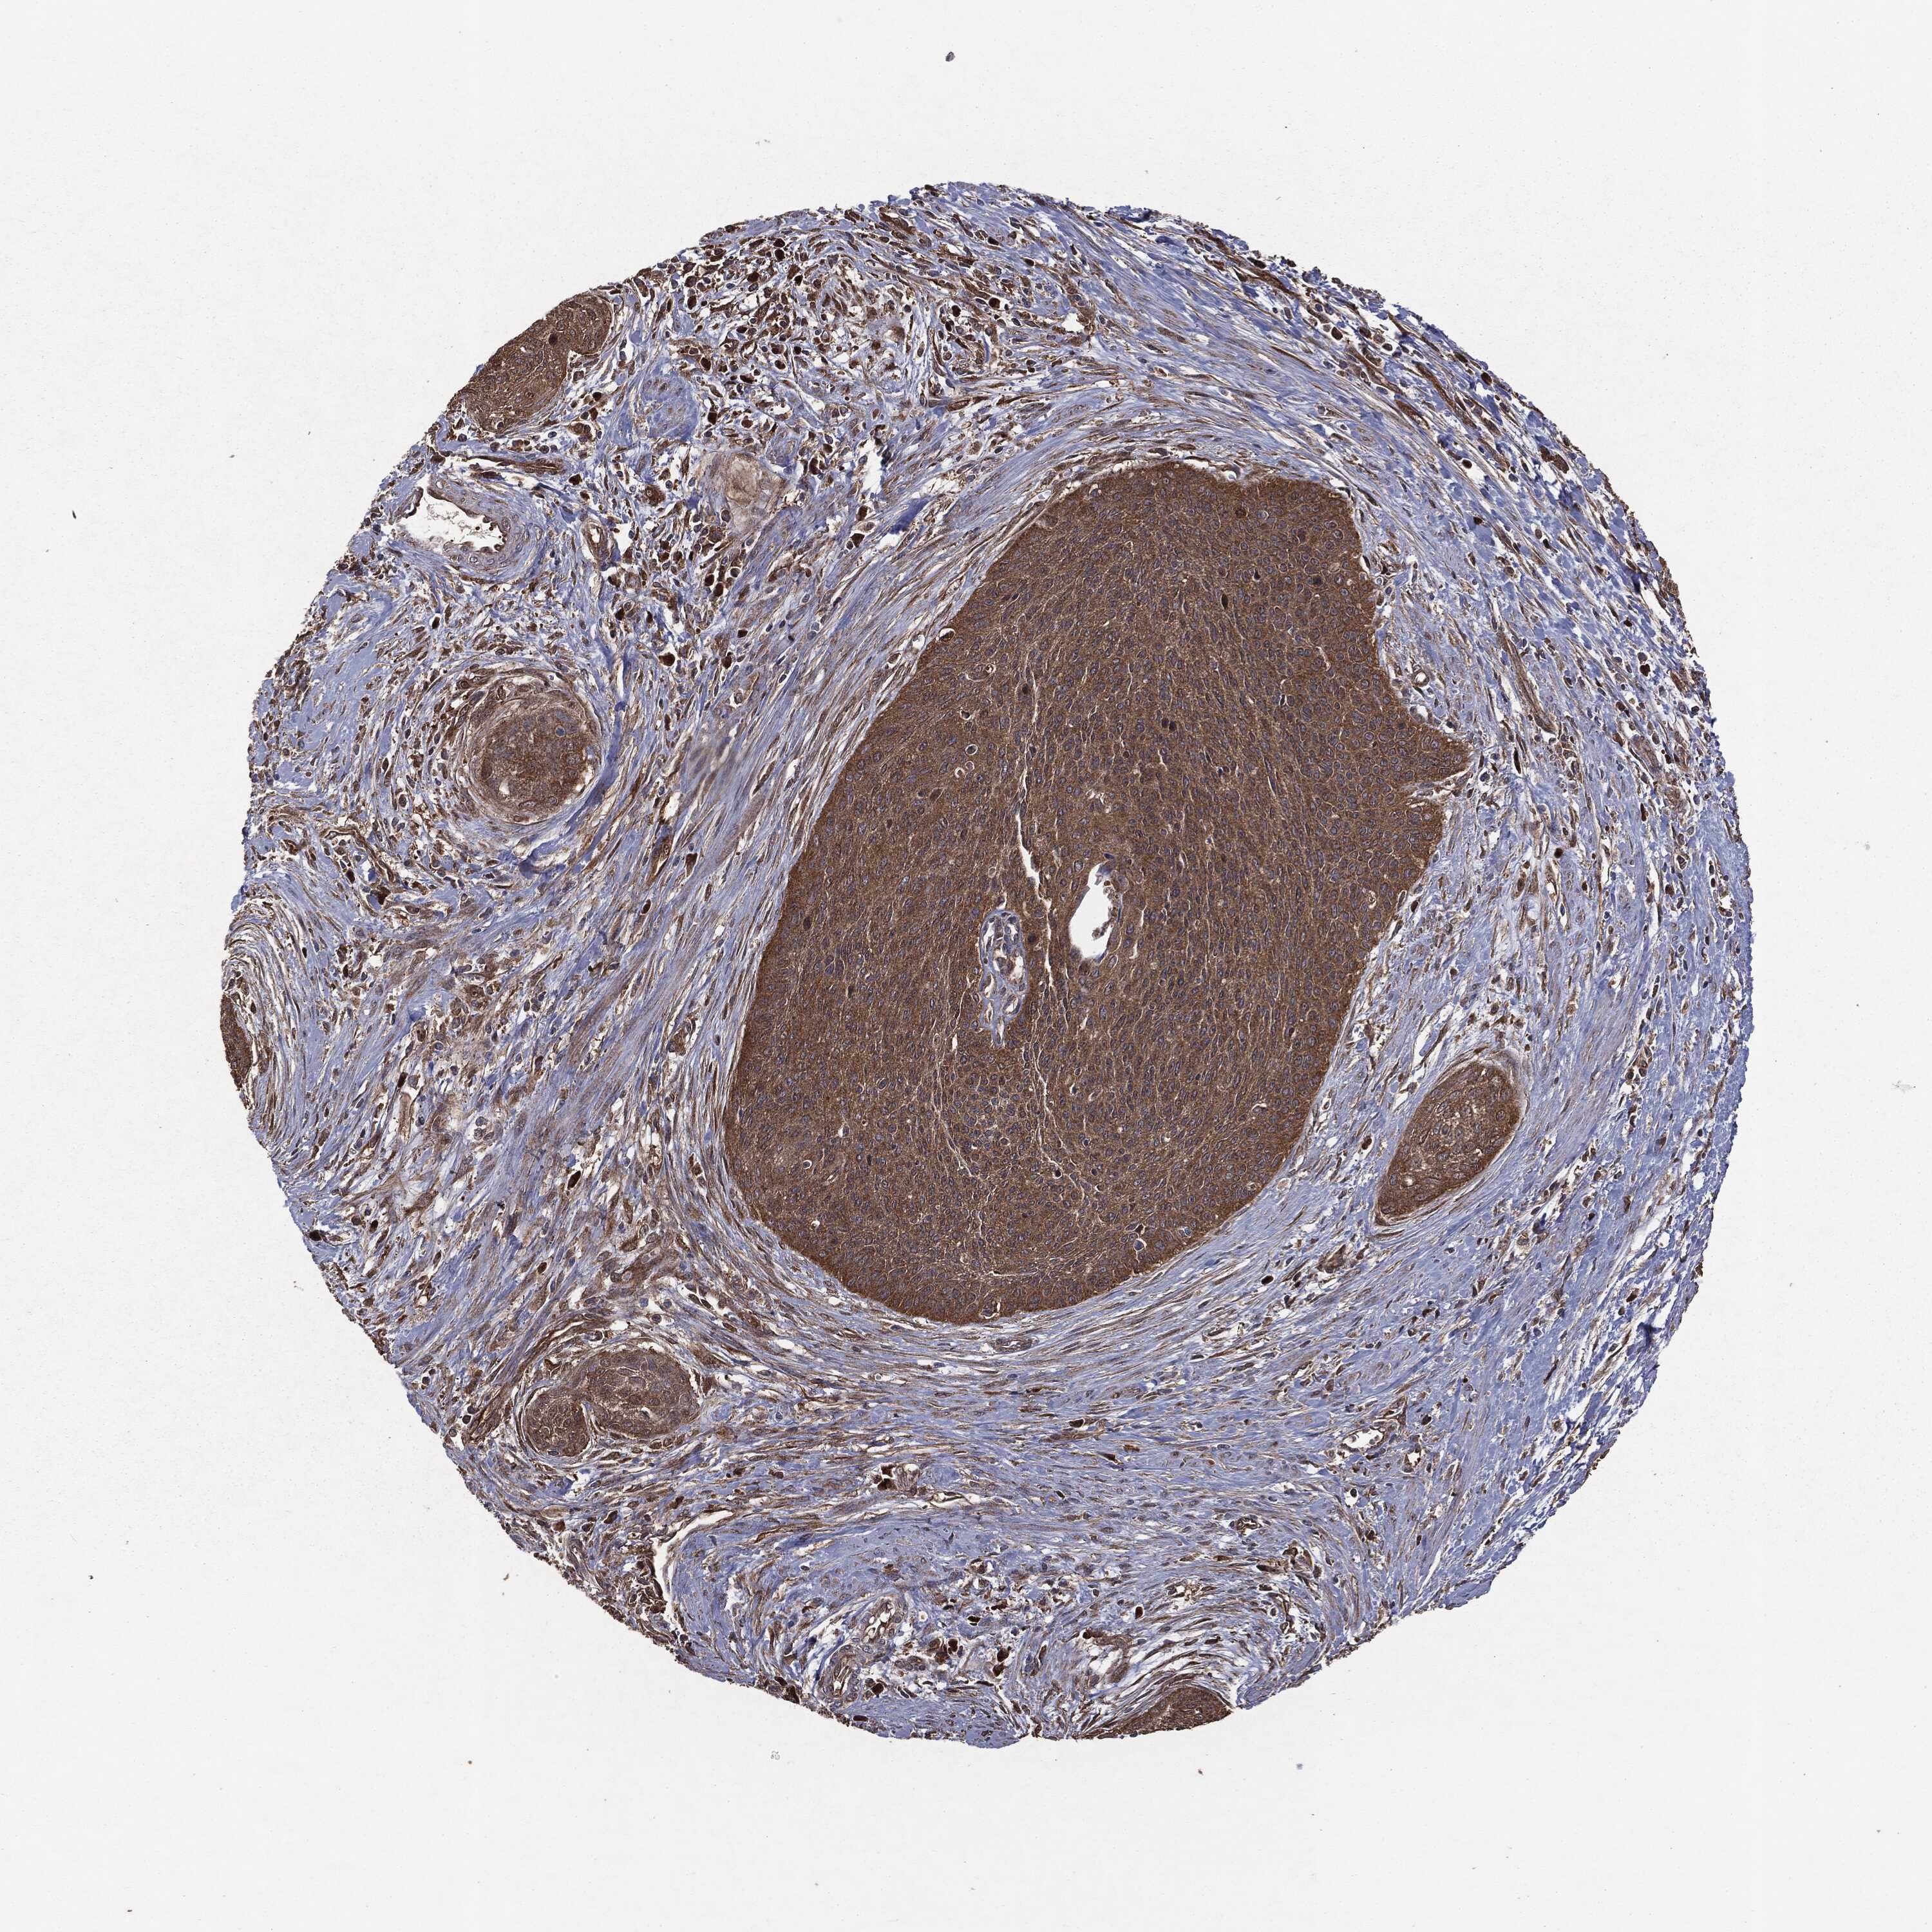

CERVICAL CANCER - Protein expressioni

A mouse-over function shows sample information and annotation data. Click on an image to view it in a full screen mode. Samples can be filtered based on level of antibody staining by selecting one or several of the following categories: high, medium, low and not detected. The assay and annotation is described here.

Note that samples used for immunohistochemistry by the Human Protein Atlas do not correspond to samples in the TCGA dataset.

Antibody stainingi

Antibody staining in the annotated cell types in the current human tissue is reported as not detected, low, medium, or high, based on conventional immunohistochemistry profiling in selected tissues. This score is based on the combination of the staining intensity and fraction of stained cells.

Each image is clickable and will lead to virtual microscopy that enables deeper exploration of all samples and also displays staining intensity scores, fraction scores and subcellular localization as well as patient and tissue information for each sample.

HPA008467

HPA041113

CAB040571

CAB080149

CAB080151

CAB080152

Staining

High

Medium

Low

Not detected

Intensity

Strong

Moderate

Weak

Negative

Quantity

>75%

75%-25%

<25%

None

Location

Nuclear

Cytoplasmic/membranous

Cytoplasmic/membranous,nuclear

Squamous cell carcinoma, NOS

Adenocarcinoma, NOS